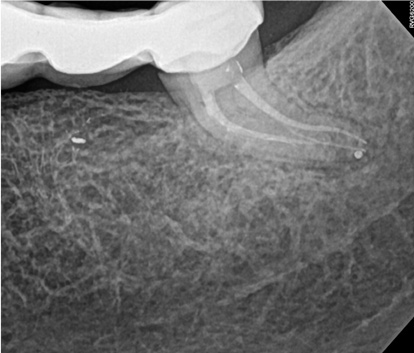

Fig 9. Case 2: Significant bone loss on the mesial and apical aspect suggested a potential vertical fracture (Fig 9 and Fig 10). Radiographic images were taken immediately postoperatively (Fig 11) and 7 months postoperatively (Fig 12).

Fig 10. Case 2: Significant bone loss on the mesial and apical aspect suggested a potential vertical fracture (Fig 9 and Fig 10). Radiographic images were taken immediately postoperatively (Fig 11) and 7 months postoperatively (Fig 12).

Fig 11. Case 2: Significant bone loss on the mesial and apical aspect suggested a potential vertical fracture (Fig 9 and Fig 10). Radiographic images were taken immediately postoperatively (Fig 11) and 7 months postoperatively (Fig 12).

Fig 12. Case 2: Significant bone loss on the mesial and apical aspect suggested a potential vertical fracture (Fig 9 and Fig 10). Radiographic images were taken immediately postoperatively (Fig 11) and 7 months postoperatively (Fig 12).

The second case study is that of a healthy 88-year-old woman who presented with significant bone loss on the mesial and apical aspect of tooth No. 18, which would suggest potentially a vertical fracture in the tooth (Figure 9 and Figure 10). The clinician had initially recommended extraction, which they informed the patient would likely be the best course of action, especially given that she had plenty of bone anterior to the tooth to place implants. When the recommendation of extraction was made to the referring dentist, he had some resistance because both he and the patient were interested in saving the tooth. Although the clinician initially stood firm on the recommendation, he received a call from the general dentist about a month later. He further expressed their desire to save the tooth, and he asked if the endodontist thought the new technology, the GentleWave Procedure, could be a solution. The informed consent was obtained and the patient was scheduled for treatment. Because the canal was quite calcified apically, a defined working length could not be determined. Obturation was performed using warm vertical condensation of gutta-percha.

As indicated in Figure 11, the mesial aspect of the distal canal was never touched by instruments, yet he was able to clean, evidenced by the postoperative image. In the past, a case with this level of difficulty would have required at least two appointments, with an interim medication of calcium hydroxide, but the case was treated in a single-visit appointment.  As observed 7 months later (Figure 12), the patient returned completely asymptomatic, and complete bone healing had occurred that exceeded initial expectations.